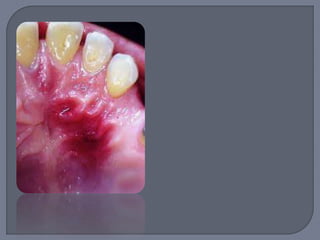

No representa una verdadera

neoplasia

Lesión reactiva causada por

irritación local o trauma

Anteriormente llamado

“granuloma reparativo de

células gigantes”

o Exclusivamente en encía o sobre borde alveolar

edéntulo

o Masa nodular de color rojo-azulado

o Sésil o pediculado

o Ulcerada o no

o Alrededor de 2 cm de

diámetro

Apariencia similar a granuloma

piógeno pero más violáceo

Se desarrolla a cualquier edad

Ligera predilección por los 50 y

60 años

60% de los casos en mujeres

Llega a haber reabsorción de

hueso subyacente

Escisión quirúrgica local por debajo del hueso

subyacente

Rebajar cuidadosamente el diente adyacente

para minimizar recidiva